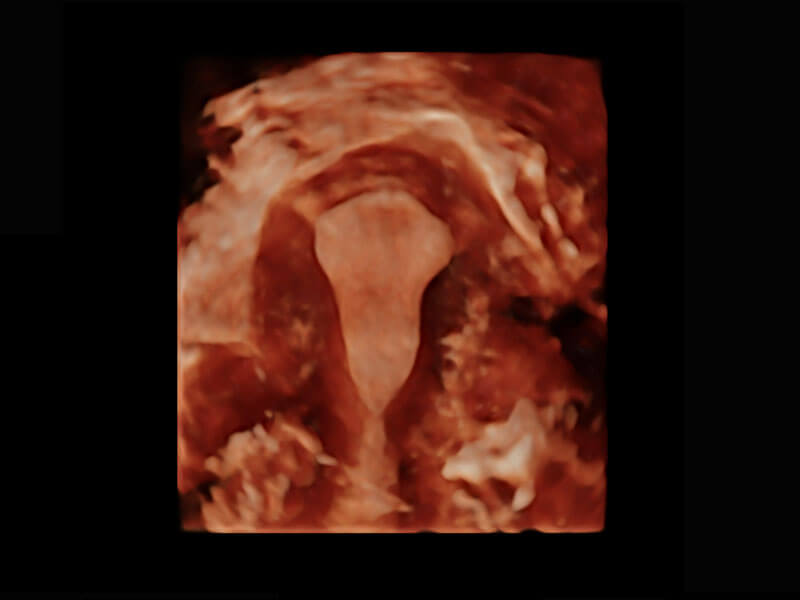

P60为盆底超声检查提供应用方案,多种腔内及腹部容积探头提供从二维、三维到四维的优异图像品质,实时快速三维容积数据获取,专业的测量工具包等人性化设计,为超声医生诊断提供有力保障。

能够简化盆底检查的操作流程,可在二维模式及三维成像模式下实现一键自动提取出标准切面、自动识别当前切面、自动测量,提升盆底检查的高效性,同时也能让青年医生快捷的获得准确的检查结果。